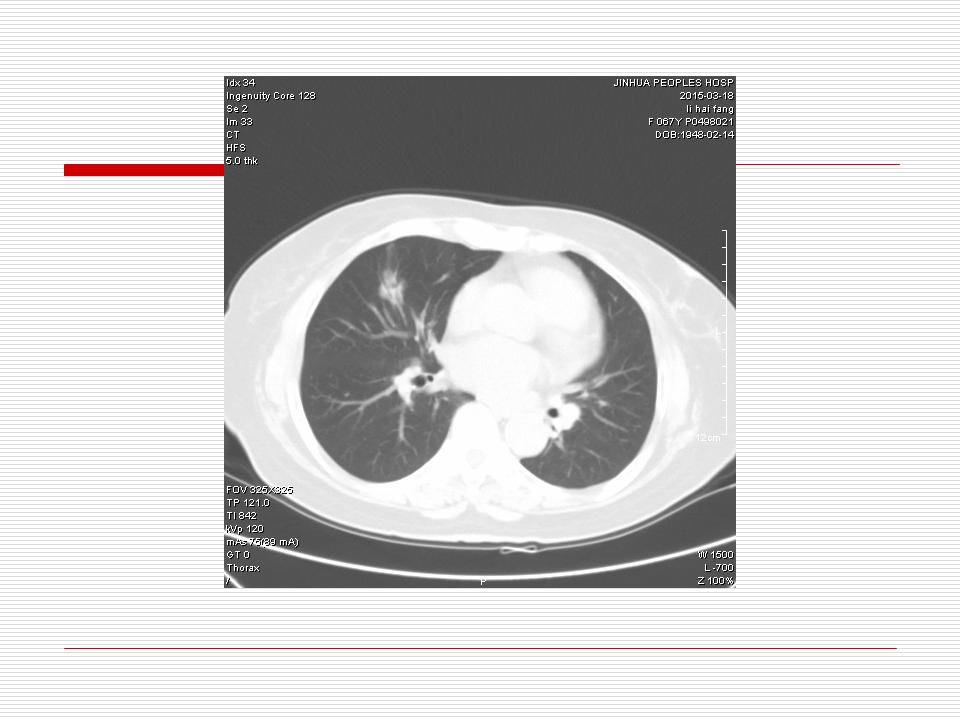

肺部阴影永恒且最重需要鉴别的是:到底是炎症还是肿瘤?但临床的病例中的影像表现难以界定或有些肿瘤特征,同时又有些炎症特点是非常常见的情况。作为临床医生我们怎么去总结分析,并找到之所以是炎症或之所以是肿瘤的细微差别或特点非常重要,也非常有用。2019.12.7浙江省2019年胸心外科学学术年会在宁波召开时,我的临床病例分析与经验总结<那些像肺癌的炎症与像炎症的肺癌>获得在大会交流的机会,以下为该PPT的内容,与你分享,希望对同道有益,有借鉴与启迪。若有探讨与进一不完善的建议,欢迎文末留言讨论: